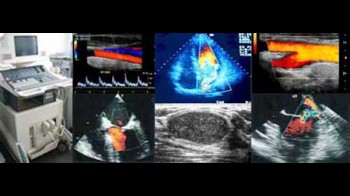

Ultrazvučni pregledi s kolor doplerom

- Ultrazvuk štitnjače

- Kolor dopler krvnih žila vrata, ekstremiteta

- Ultrazvuk vrata

- Ultrazvuk dojki

- Ultrazvuk abdomena i prostate kod muškaraca

- Ultrazvuk testisa

Ultrazvuk je kompletno neškodljiv način pregleda unutarnjih organa s mogučnošću 3D i 4D prikaza, te s mogućnošću punkcije nađenih promjena.